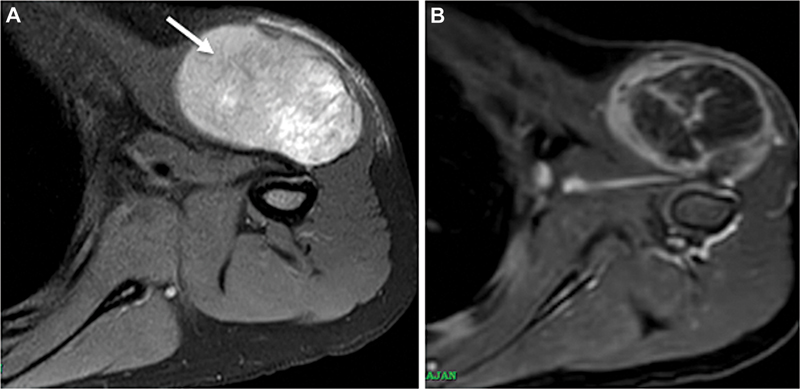

A 5-year-old male child presented with a gradually progressive mass lesion over the left shoulder region for the past 2 weeks. On local examination, there was a 4 × 5 cm mass over the anterior aspect of the shoulder, fixed to the deltoid muscle, as seen on the magnetic resonance imaging scan ([Fig. 1]). The patient underwent a needle biopsy, and histopathology showed a malignant small round cell tumor (MSRCT). On the first immunohistochemistry (IHC) panel, the tumor cells were diffusely positive for NKX2.2, CD99, Desmin, Myogenin, and MyoD1, while being negative for Pancytokeratin, LCA, Synaptophysin, and NKX3.1 ([Fig. 2]). In view of the ambiguous IHC findings, additional tests, including MUC-4 and ALK-1 ([Fig. 3]), were performed. Both showed diffuse positive expression, and a final diagnosis of Rhabdomyosarcoma (RMS) was rendered. Subsequently, break-apart fluorescence in situ hybridization (BA-FISH) revealed FOXO1 gene rearrangement in 75% of the tumor cells, clinching the diagnosis of Alveolar RMS (fusion positive) with aberrant diffuse NKX2.2 immunoexpression.

Fig 1:T2-weighted MRI showing a hyperintense soft tissue mass in the left shoulder with heterogeneous enhancement, involving the deltoid muscle (arrow). No erosion of underlying bone seen.